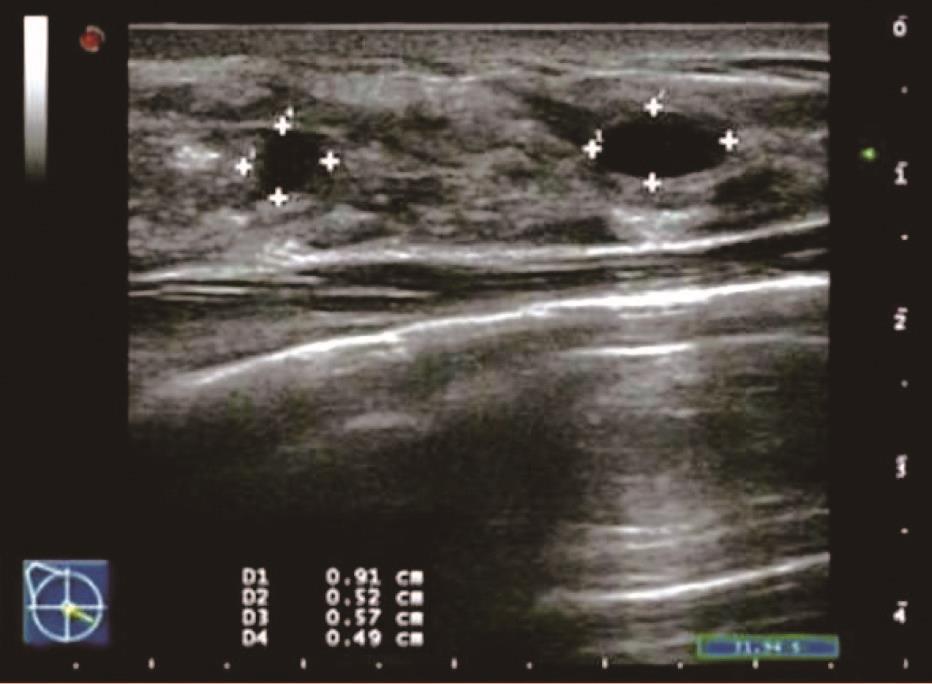

患者,女,35岁,因双乳疼痛两月,乳头偶有针刺状疼痛,感到胸闷,呼吸不畅来院诊治。超声检查结果显示:右乳内可见多个无回声区,边界清晰,形态规则,其中3点方向较大一个1.7*0.6cm,内可见分隔光带,左乳内可见数个无回声区,边界清晰,形态规则,其中3点方向较大一个大小1.1*0.6cm内可见分隔光带,CDFI探查:未见异常血流信号显示。双侧乳腺切面形态轮廓正常,层次清楚。腺体厚薄不均,边界完整,欠规则,结构紊乱,分布不均,呈片状高回声区。

超声提示:两侧乳腺增生。